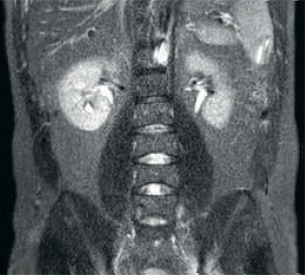

Result: Improved SNR and image resolution

Result: Noisy images using identical scan parameters